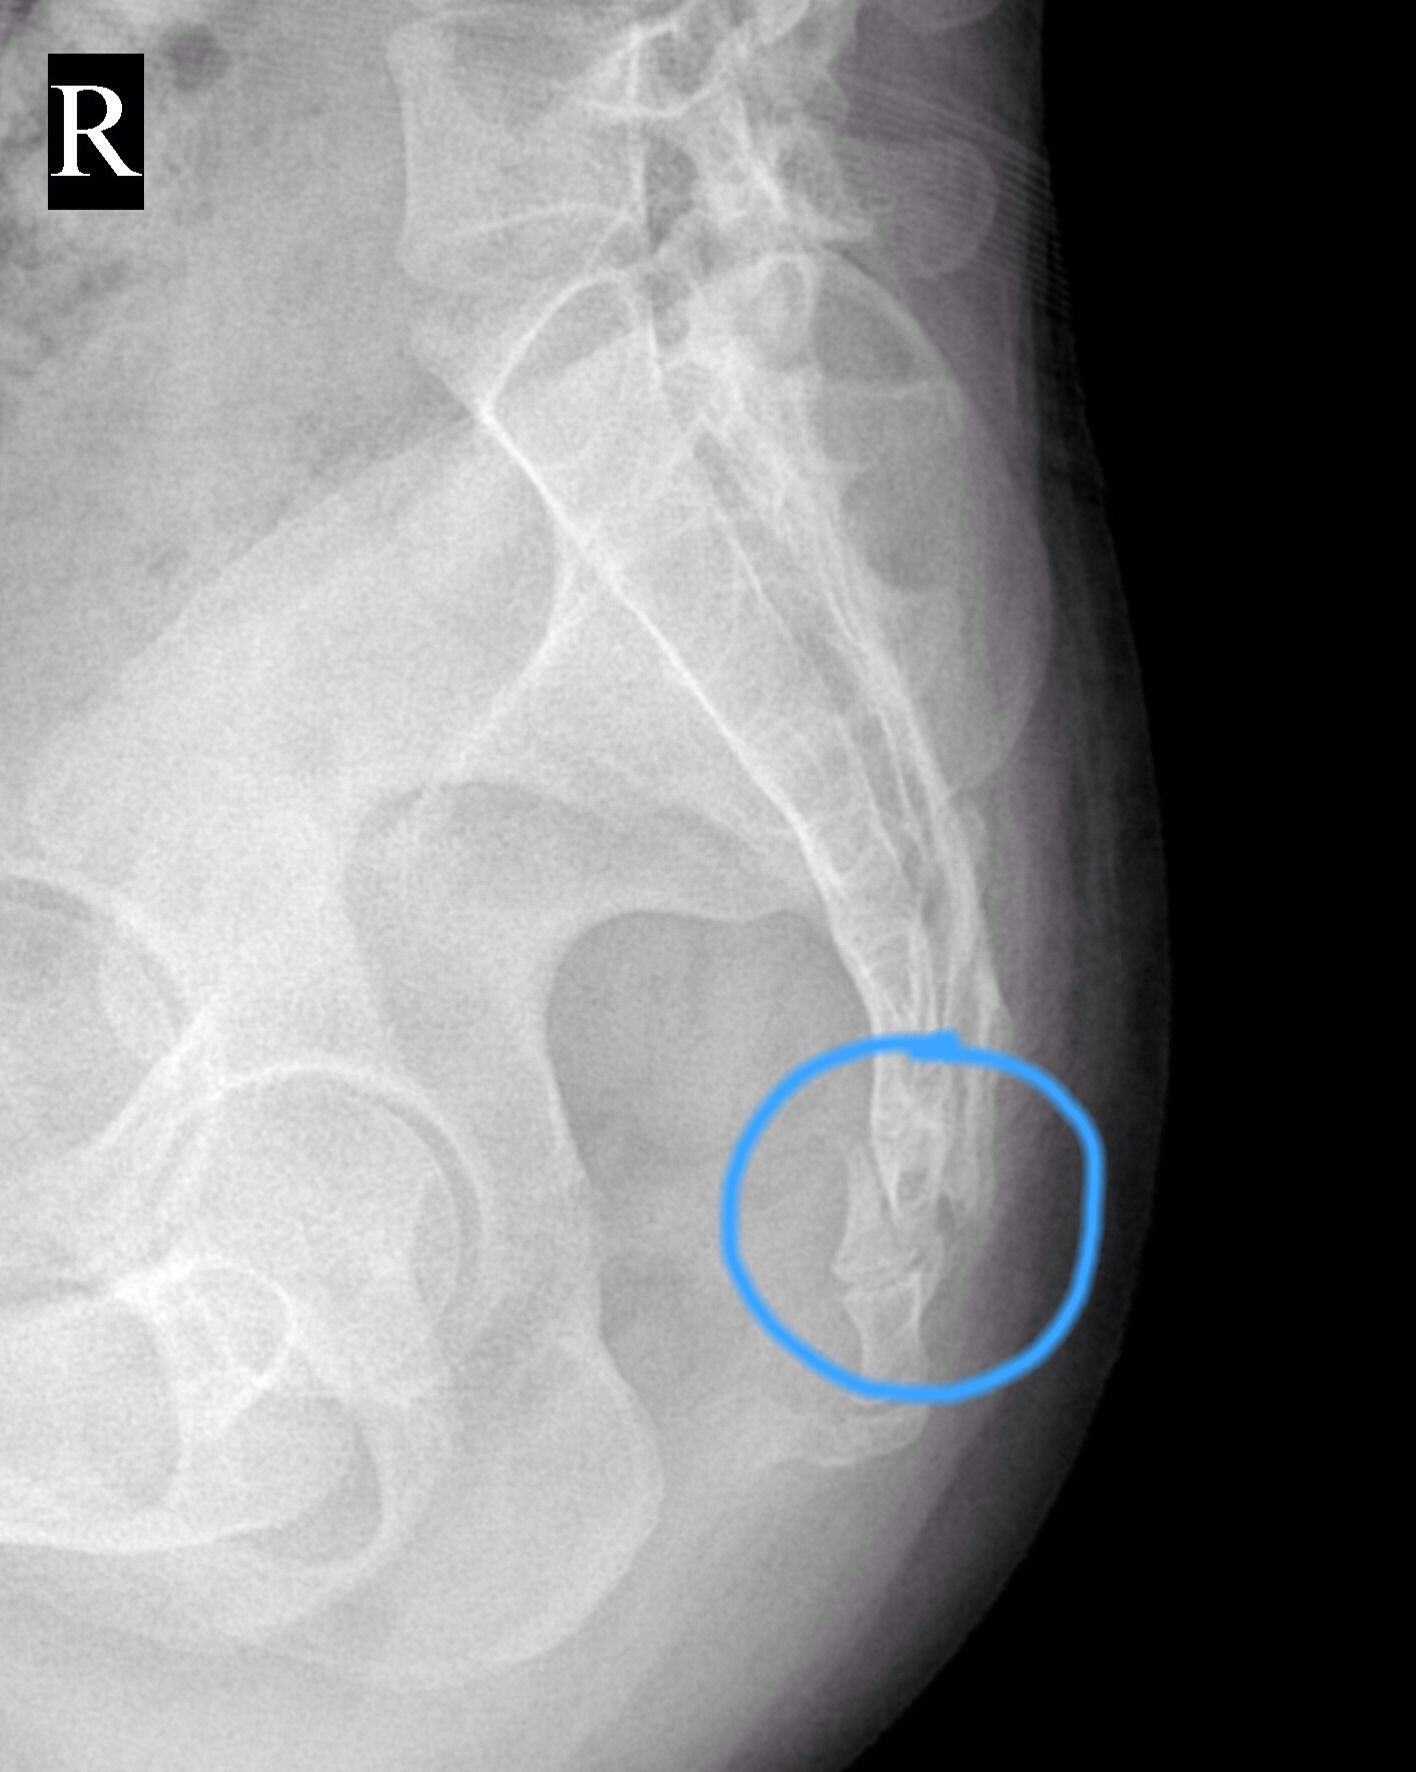

1例尾骨骨折并脱位

图片尺寸985x1512